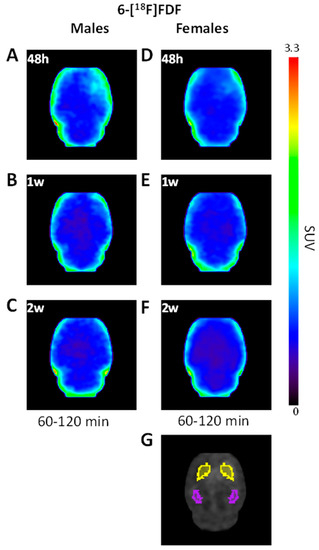

2.1. Early Increase in 6-[18F]FDF Uptake in LPS-Injected Striatum